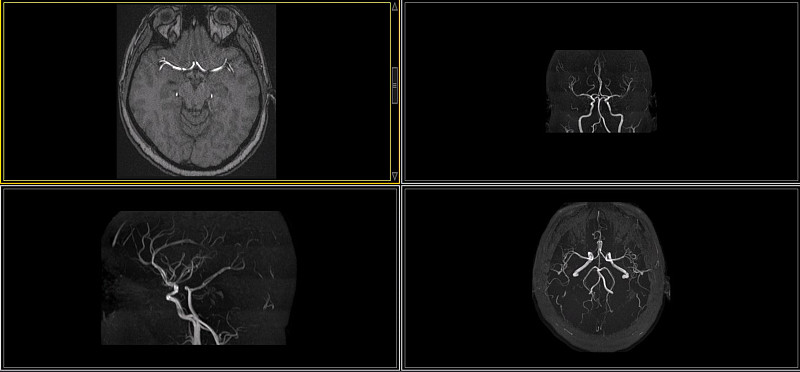

冠状动脉海葵详情

JPG